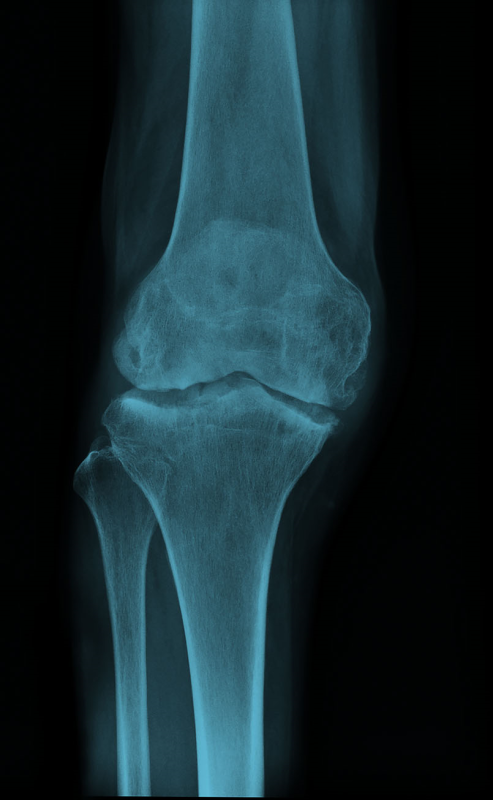

Запитання 23

НЕОПЕРОВАНИЙ ПЕРЕЛОМ ЦІЄЇ КІСТКИ І В ЦЬОМУ МІСЦІ ПРИЗВЕДЕ ДО СМЕРТІ В СЕРЕДНЬОМУ ЧЕРЕЗ КІЛЬКА РОКІВ. А ЦІ РОКИ ПЕРЕТВОРЯТЬСЯ НА СИДЯЧІ АБО ЛЕЖАЧІ МУКИ. ЯКОЇ КІСТКИ І ЯКОЇ ЇЇ ЧАСТИНИ?

варіанти відповідей

HUMERUS, ХІРУРГІЧНА ШИЙКА

ВЕРХНЬОГО ДІАФІЗА

FEMUR, ШИЙКА

ULNA, ШИЙКА

ПРОКСИМАЛЬНОГО ЕПІФІЗА

ДИСТАЛЬНОГО ЕПІФІЗА

HUMERUS, ШИЙКА

RADIUS, ШИЙКА